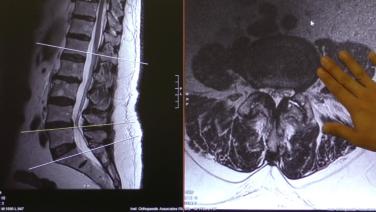

Abordaje por vía anterior al psoas (ATP): planificación preoperatoria con el Dr. Chi Lim